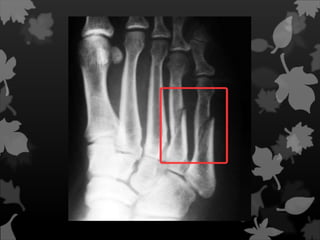

Essa fratura seinstala vagarosamente devido à confluência de microfraturas que surgem em decorrência de pequenos traumatismos ou esforços aplicados ciclicamente no osso. Está muito relacionada com atividades esportivas ou profissionais como, por exemplo, a fratura do terço proximal da tíbia na bailarina e a fratura de metatarsais em recrutas do exército que fazem marcha forçada.

 Estresse ou fadiga

Está muito relacionada com

atividades esportivas ou profissionais

como, por exemplo, a fratura do terço

proximal da tíbia na bailarina e a fratura

de metatarsais em recrutas do exército

que fazem marcha forçada.